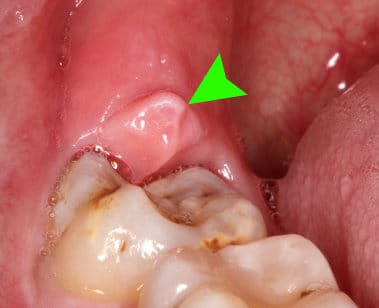

Ampolla en el trígono retromolar

Hace aproximadamente un mes y medio tengo una ampolla en esa zona de la boca, es bastante molesta y no desaparece, a veces revienta y me da alivio pero nunca se termina de ir, ¿Qué podría ser?